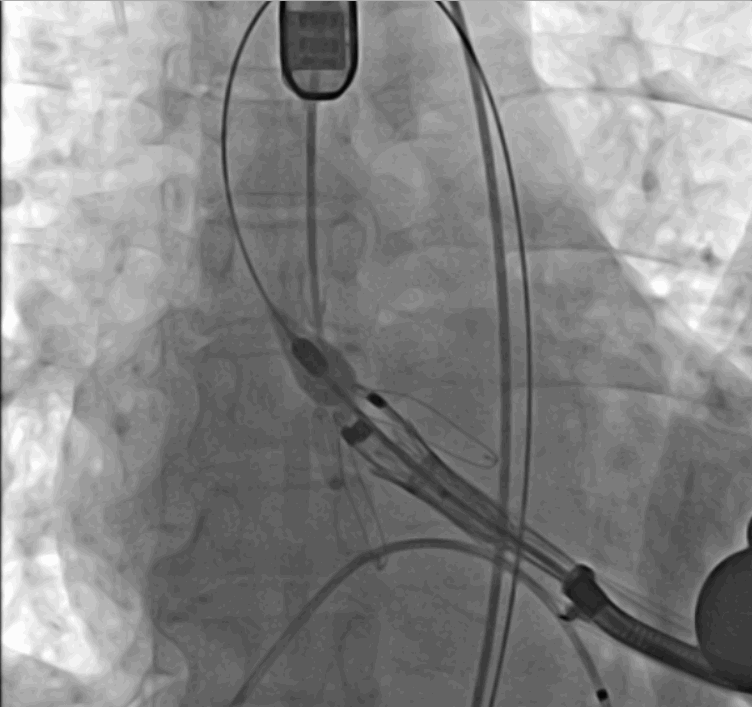

術(shù)中瓣膜釋放過(guò)程